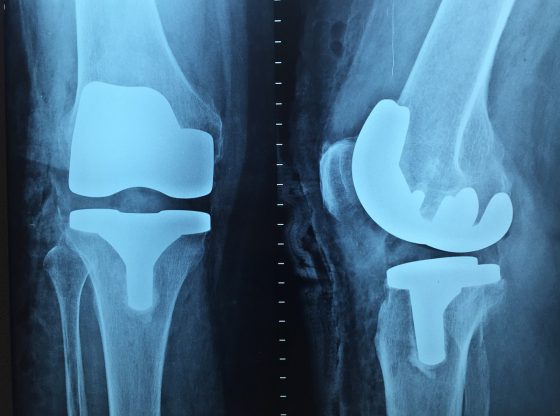

Centrum Medyczne Gamma w Warszawie wychodzi naprzeciw oczekiwaniom pacjentów, którzy szukają punktu z dużą ilością usług medycznych. To właśnie tu funkcjonuje ostry dyżur, poradnie specjalistyczne, szpital, a także sale rehabilitacyjne.…